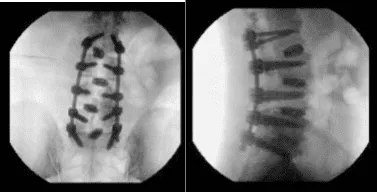

Se introdujo la navegación y se realizó una tomografía computarizada. Tras verificar la navegación, se colocaron tornillos pediculares a ambos lados de L2 a S1 secuencialmente bajo guía de navegación tras usar el cambio de marchas, que se golpeaban y comprobaban cada vez con una sonda de punta de bola.

Se lograron posiciones aceptables en todos los niveles. La punta del destornillador estaba rota en el tornillo derecho S1, pero se dejó en su sitio porque era difícil sacarla y habría provocado aflojamiento.

Las varillas se colocaban sobre los tornillos pediculares y se apretaban en su lugar con tornillos de fijación, y finalmente se aprietaban con un destornillador de elevación de torque. Se tomaron las fotos finales y se encontró en una posición aceptable.